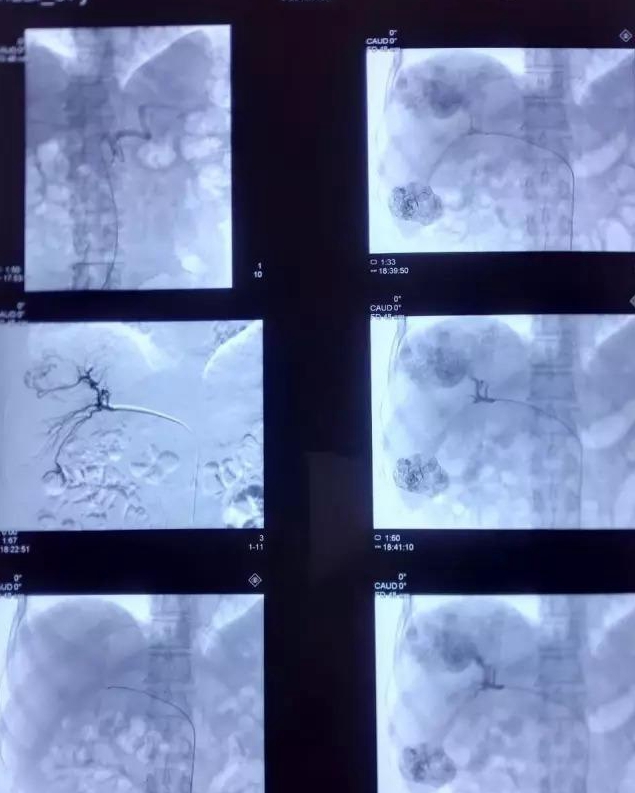

肝癌介入治療,是指經股動脈插管將抗癌藥物或栓塞劑注入肝動脈的一種區(qū)域性局部化療,是非開腹手術治療肝癌的選擇方法。我們經常說的肝癌介入治療是一種血管介入治療,可以通過栓塞把腫瘤血管堵住,使腫瘤壞死缺血縮小,或者,通過介入方法局部灌注化療藥物,使其在腫瘤區(qū)域局部藥物濃度很高,從而達到治療的目,同時,還可以聯(lián)合一些射頻消融等治療方式提高治效果果。介入治療是在局麻狀態(tài)下進行,創(chuàng)傷小,恢復快,效果好。

循證醫(yī)學證據(jù)業(yè)已表明肝癌介入治療能有效控制肝癌生長,明顯延長患者生存期,使肝癌患者獲益,已成為不能手術切除的中晚期肝癌重要的治療方法。

術后